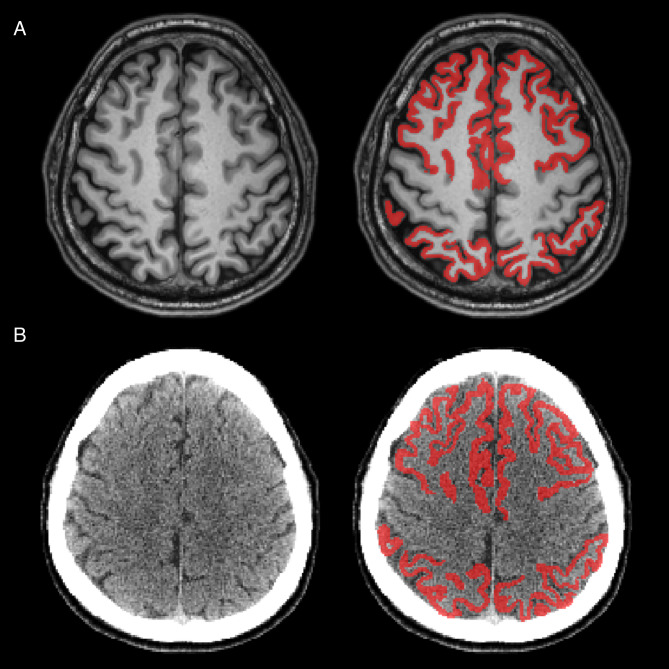

背景:淀粉样蛋白PET/CT对于量化阿尔茨海默病(AD)中淀粉样蛋白- β (Aβ)沉积至关重要,Centiloid (CL)量表标准化了跨成像中心的测量。然而,基于mri的CL管道面临着挑战:高成本、禁忌症和患者负担。为了解决这些挑战,我们开发了一种基于深度学习的CT分割管道,使用PET/CT扫描的CT图像校准到标准CL尺度,并评估其相对于标准管道的性能。方法:共有306名参与者(23名年轻对照[YCs]和283名患者)接受了18次F-florbetaben (FBB) PET/CT和MRI检查。经目测,a β阳性207例,a β阴性76例。PET图像使用CT包裹管道处理,并与FreeSurfer (FS)和标准管道进行比较。通过回归分析评估一致性。使用效应大小、方差和ROC分析来比较管道,并确定相对于视觉Aβ评估的最佳CL阈值。结果:CT分片与FS一致性高,定量CL可靠(R²= 0.99)。这两个管道在YCs和ADCI之间显示出相似的差异和效应大小。ROC分析证实了相当的准确性和相似的CL阈值,支持CT分割作为可行的无mri替代方法。结论:我们的研究结果表明,CT包裹管道在CL量化方面达到了与FS相似的准确度水平,证明了其作为无mri替代方案的可靠性。在PET/CT中,CT和PET在同一时间段内在共用床和头枕上依次获得,这有助于保持一致的定位和适当的空间对齐,减少配准误差,支持更可靠和精确的量化。

Background: Amyloid PET/CT is essential for quantifying amyloid-beta (Aβ) deposition in Alzheimer's disease (AD), with the Centiloid (CL) scale standardizing measurements across imaging centers. However, MRI-based CL pipelines face challenges: high cost, contraindications, and patient burden. To address these challenges, we developed a deep learning-based CT parcellation pipeline calibrated to the standard CL scale using CT images from PET/CT scans and evaluated its performance relative to standard pipelines.

Methods: A total of 306 participants (23 young controls [YCs] and 283 patients) underwent 18 F-florbetaben (FBB) PET/CT and MRI. Based on visual assessment, 207 patients were classified as Aβ-positive and 76 as Aβ-negative. PET images were processed using the CT parcellation pipeline and compared to FreeSurfer (FS) and standard pipelines. Agreement was assessed via regression analyses. Effect size, variance, and ROC analyses were used to compare pipelines and determine the optimal CL threshold relative to visual Aβ assessment.

Results: The CT parcellation showed high concordance with the FS and provided reliable CL quantification (R² = 0.99). Both pipelines demonstrated similar variance in YCs and effect sizes between YCs and ADCI. ROC analyses confirmed comparable accuracy and similar CL thresholds, supporting CT parcellation as a viable MRI-free alternative.

Conclusions: Our findings indicate that the CT parcellation pipeline achieves a level of accuracy similar to FS in CL quantification, demonstrating its reliability as an MRI-free alternative. In PET/CT, CT and PET are acquired sequentially within the same session on a shared bed and headrest, which helps maintain consistent positioning and adequate spatial alignment, reducing registration errors and supporting more reliable and precise quantification.